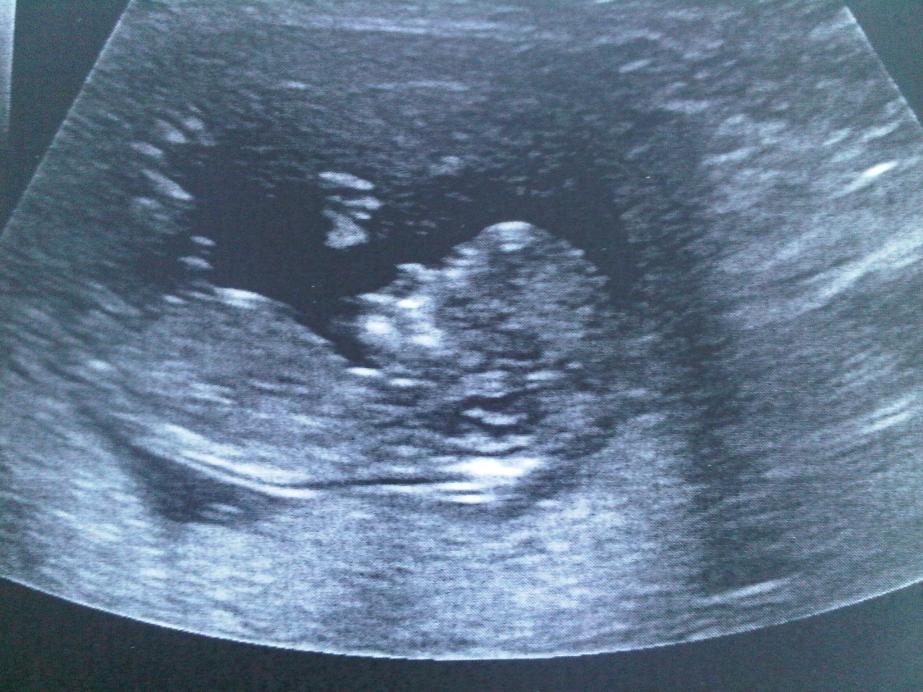

Does anyone see any gender clues in my 12 wk U/S? (In reply 4)

It's pretty fuzzy in the nub area, but from what I can see here..... I'm really thinking :DD:!!! I hope I'm right!!!:HH: When is your next scan???

Ooh tweedle, so exciting, how did I miss stalking you?! I'm guessing girl from what I see but it is fuzzy. Can you edit the photo at all? I found that playing with the contrast and brightness made everything a lot clearer!

Can anyone tell me which part is the nub? I'm not sure which part to look at. I will check my other photo too.

I hope you don't mind Tweedle....I photoshopped it to show you:) I think it could be either of the 2 marked spots...not sure which but both look VERY GIRLIE! I made lines to show you what I was looking at...I'd be willing to put money on a GIRL:bigsmile: